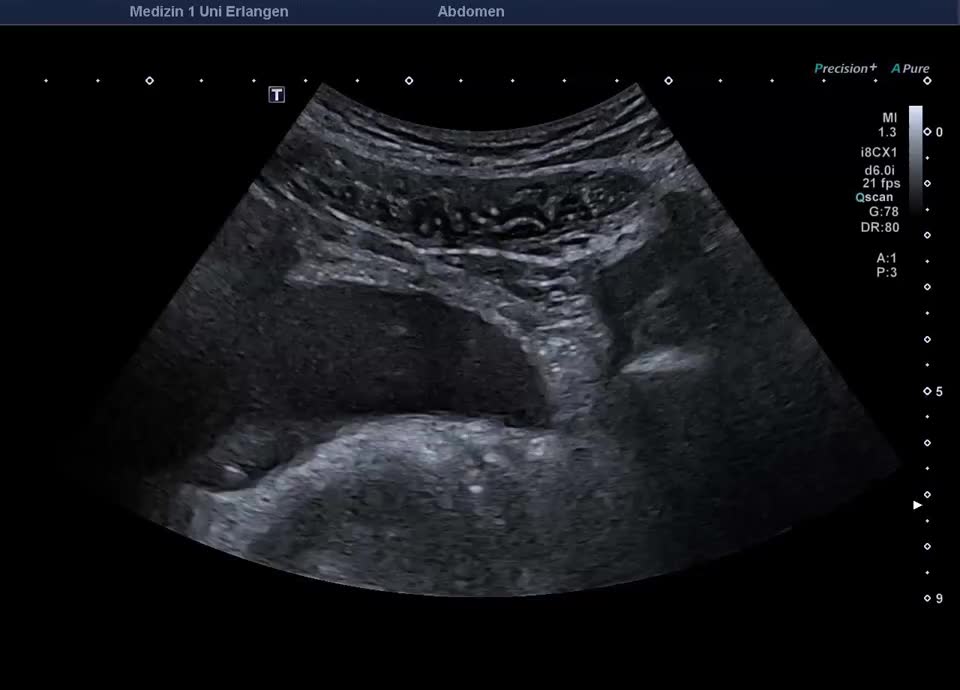

55-jähriger Patient mit abdominellen Beschwerden. Sonographisch stellt sich die linke Niere mit einem altersentsprechenden Parenchymsaum und regelrechter Mark-/Rindendifferenzierung dar. Das Nierenbeckenkelchsystem ist nicht erweitert. Distal im Bereich des Harnblasenostiums zeigt sich ein Konkrement von ca. 6 mm im Ureter, begleitet von positivem Twinkling-Artefakt im Farbdoppler. Der Ureter ist diskret erweitert, proximal bis 10mm. Sonographischer Befund vereinbar mit einer Ureterolithiasis im distalen linken Ureter (Ostium Harnblasenboden).